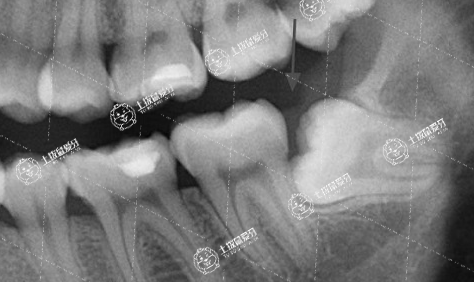

智齒不正常萌出

不一定。通常來說,需不需要拔智齒是和智齒是否萌出,萌出后位置及方向等情況有很大關(guān)系。

1、如果整牙的時候,智齒還沒有長出,那就不用管,可以先整牙。比如很多地包天患者,一般建議可以從3歲左右就開始干預(yù)了,或者11/12歲左右整牙是沒有智齒這個煩惱的。

2、如果智齒長出來了,位置不好,而且由于整牙需要一兩年的時間,擔心智齒發(fā)炎引起疼痛等不適,而且對口腔清潔影響很大,建議在整牙之前拔除智齒比較好。而且智齒本身也沒有牙齒功能,拔除后不會對正畸產(chǎn)生影響。

3、如果整牙過程中,智齒長出來了,這時候可能需要根據(jù)智齒的位置、拔除創(chuàng)口以及牙齒咬合等問題,是否可以拔除,需要專業(yè)正畸醫(yī)生來判斷。

4、如果整牙前和整牙過程中,智齒都沒有萌出,直到完整正畸后,智齒才萌出,那么這個時候,也是可以根據(jù)智齒的位置和情況確定是否需要拔除,如可能影響牙齒排列擁擠,造成牙齒畸形反彈幾率大的就要及時拔除,如正常萌出,位置方向等正常,也有對咬牙的智齒是可以保留的,不過這種情況臨床上比較少見。